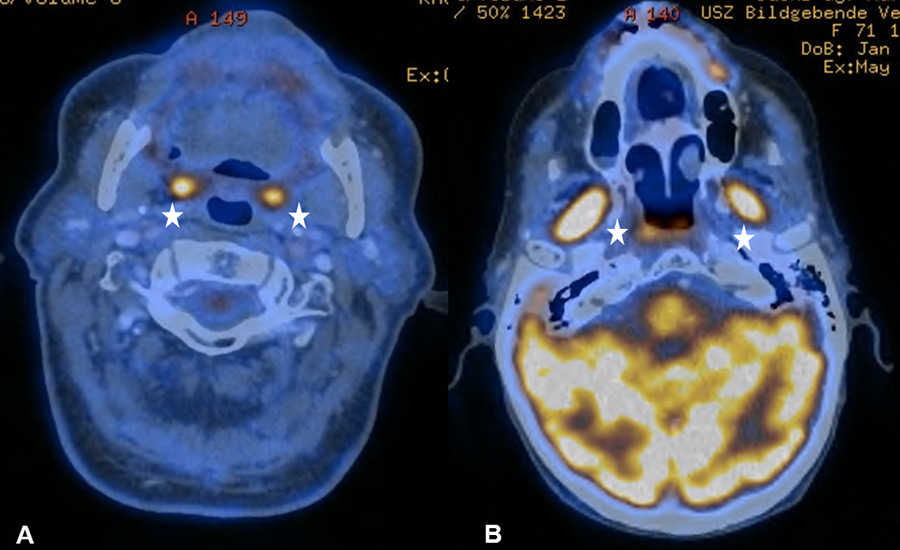

Figure 1

(A) Bilateral physiological uptake in the palatine tonsils in a 83-year old patient with a past medical history of a floor of nose melanoma. (B) Symmetric increased uptake in the muscles of mastication in 71-year old patient treated for tonsillar carcinoma.

It is known that PET-CT is more accurate in detecting HNC recurrence than conventional physical examinations alone and that therefore negative periodic clinical examinations may be complemented by FDG PET-CT [8, 15]. As expected, we observed PET-CT to be a well-established ruling-out test at the expense of a decreased positive predictive value and specificity [7–9]. However, interpretation of indistinct FDG-positive findings remains challenging because of a high number of false-positive lesions and the necessity for potentially unnecessary and invasive diagnostic investigations. As in previous studies, we found typical foci of increased FDG uptake [16, 17]. The pharyngeal mucosa frequently causes physiological FDG uptake, hence the interpretation is usually unproblematic as long as the uptake is located superficially along the mucosal plane in linear configuration [18]. The palatine tonsils and other lymphatic structures of the Waldeyer’s ring typically exhibit FDG uptake, which most likely reflects a so-called “physiological inflammation” of the lymphatic tissue due to confrontation with antigens [18, 19] (fig. 1A). Furthermore, muscles of mastication and intrinsic tongue muscles were shown to be highly sensitive to exogenous confounders such as chewing gum during examination and therefore a good quality of PET-CT/MRI clearly depends on the compliance of the patient [20, 21] (fig. 1B). With regard to the floor of mouth (FOM) muscles, a recent study investigating the effect of a supine versus a sitting position on physiological FDG accumulation, did not find any alterations and concluded that there is no trick to avoid or reduce this kind of disturbing FDG uptake [22]. The correlation between muscular activity and increased FDG uptake was also shown for the larynx, since talking can cause FDG uptake in the muscles of phonation as well as in the vocal cords [18, 23]. In terms of FDG uptake in the salivary glands, the parotid, submandibular and sublingual glands may all reveal mild to moderate symmetric or asymmetric uptake, although these findings underlie a marked inter-individual variability [16, 17]. As there is a close relationship between reduction in FDG uptake into the salivary glands and increasing doses of RT, we found five patients with asymmetric salivary gland FDG uptake due to surgical treatment and RT to the contralateral side [24] (fig. 2A). Similarly, we observed four patients with asymmetric FDG uptake in the tongue and FOM as a consequence of muscular imbalance due to contralateral surgical treatment (fig. 2B). Another well-known phenomenon is the increased FDG uptake in the contralateral vocal cord if a recurrent laryngeal nerve palsy is present (fig. 3AB).